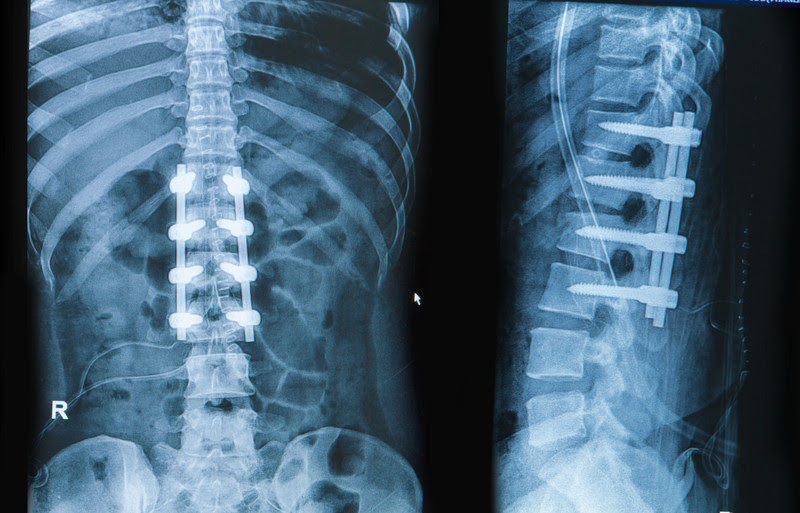

El objetivo de un tratamiento quirúrgico es la reconstrucción anatómica de la columna vertebral con estabilidad inmediata y alivio de cualquier compresión medular. La instrumentación se define como la estabilización anterior o posterior sin la fusión definitiva de los segmentos de movimiento de la articulación. La fusión espinal o "espondilodesis" se define como una fusión permanente de un segmento en movimiento La técnica de fusión posterior incluye la decorticación de la articulación intersomática, la colocación de injerto óseo autógeno o alogénico o el uso de sustitutos óseos osteoconductores y / u osteoinductores. La reconstrucción anterior se define por una restauración anatómica de la columna ventral con el uso de implantes (jaulas, instrumentación ventral), injertos u otros materiales.

Tratamiento operatorio